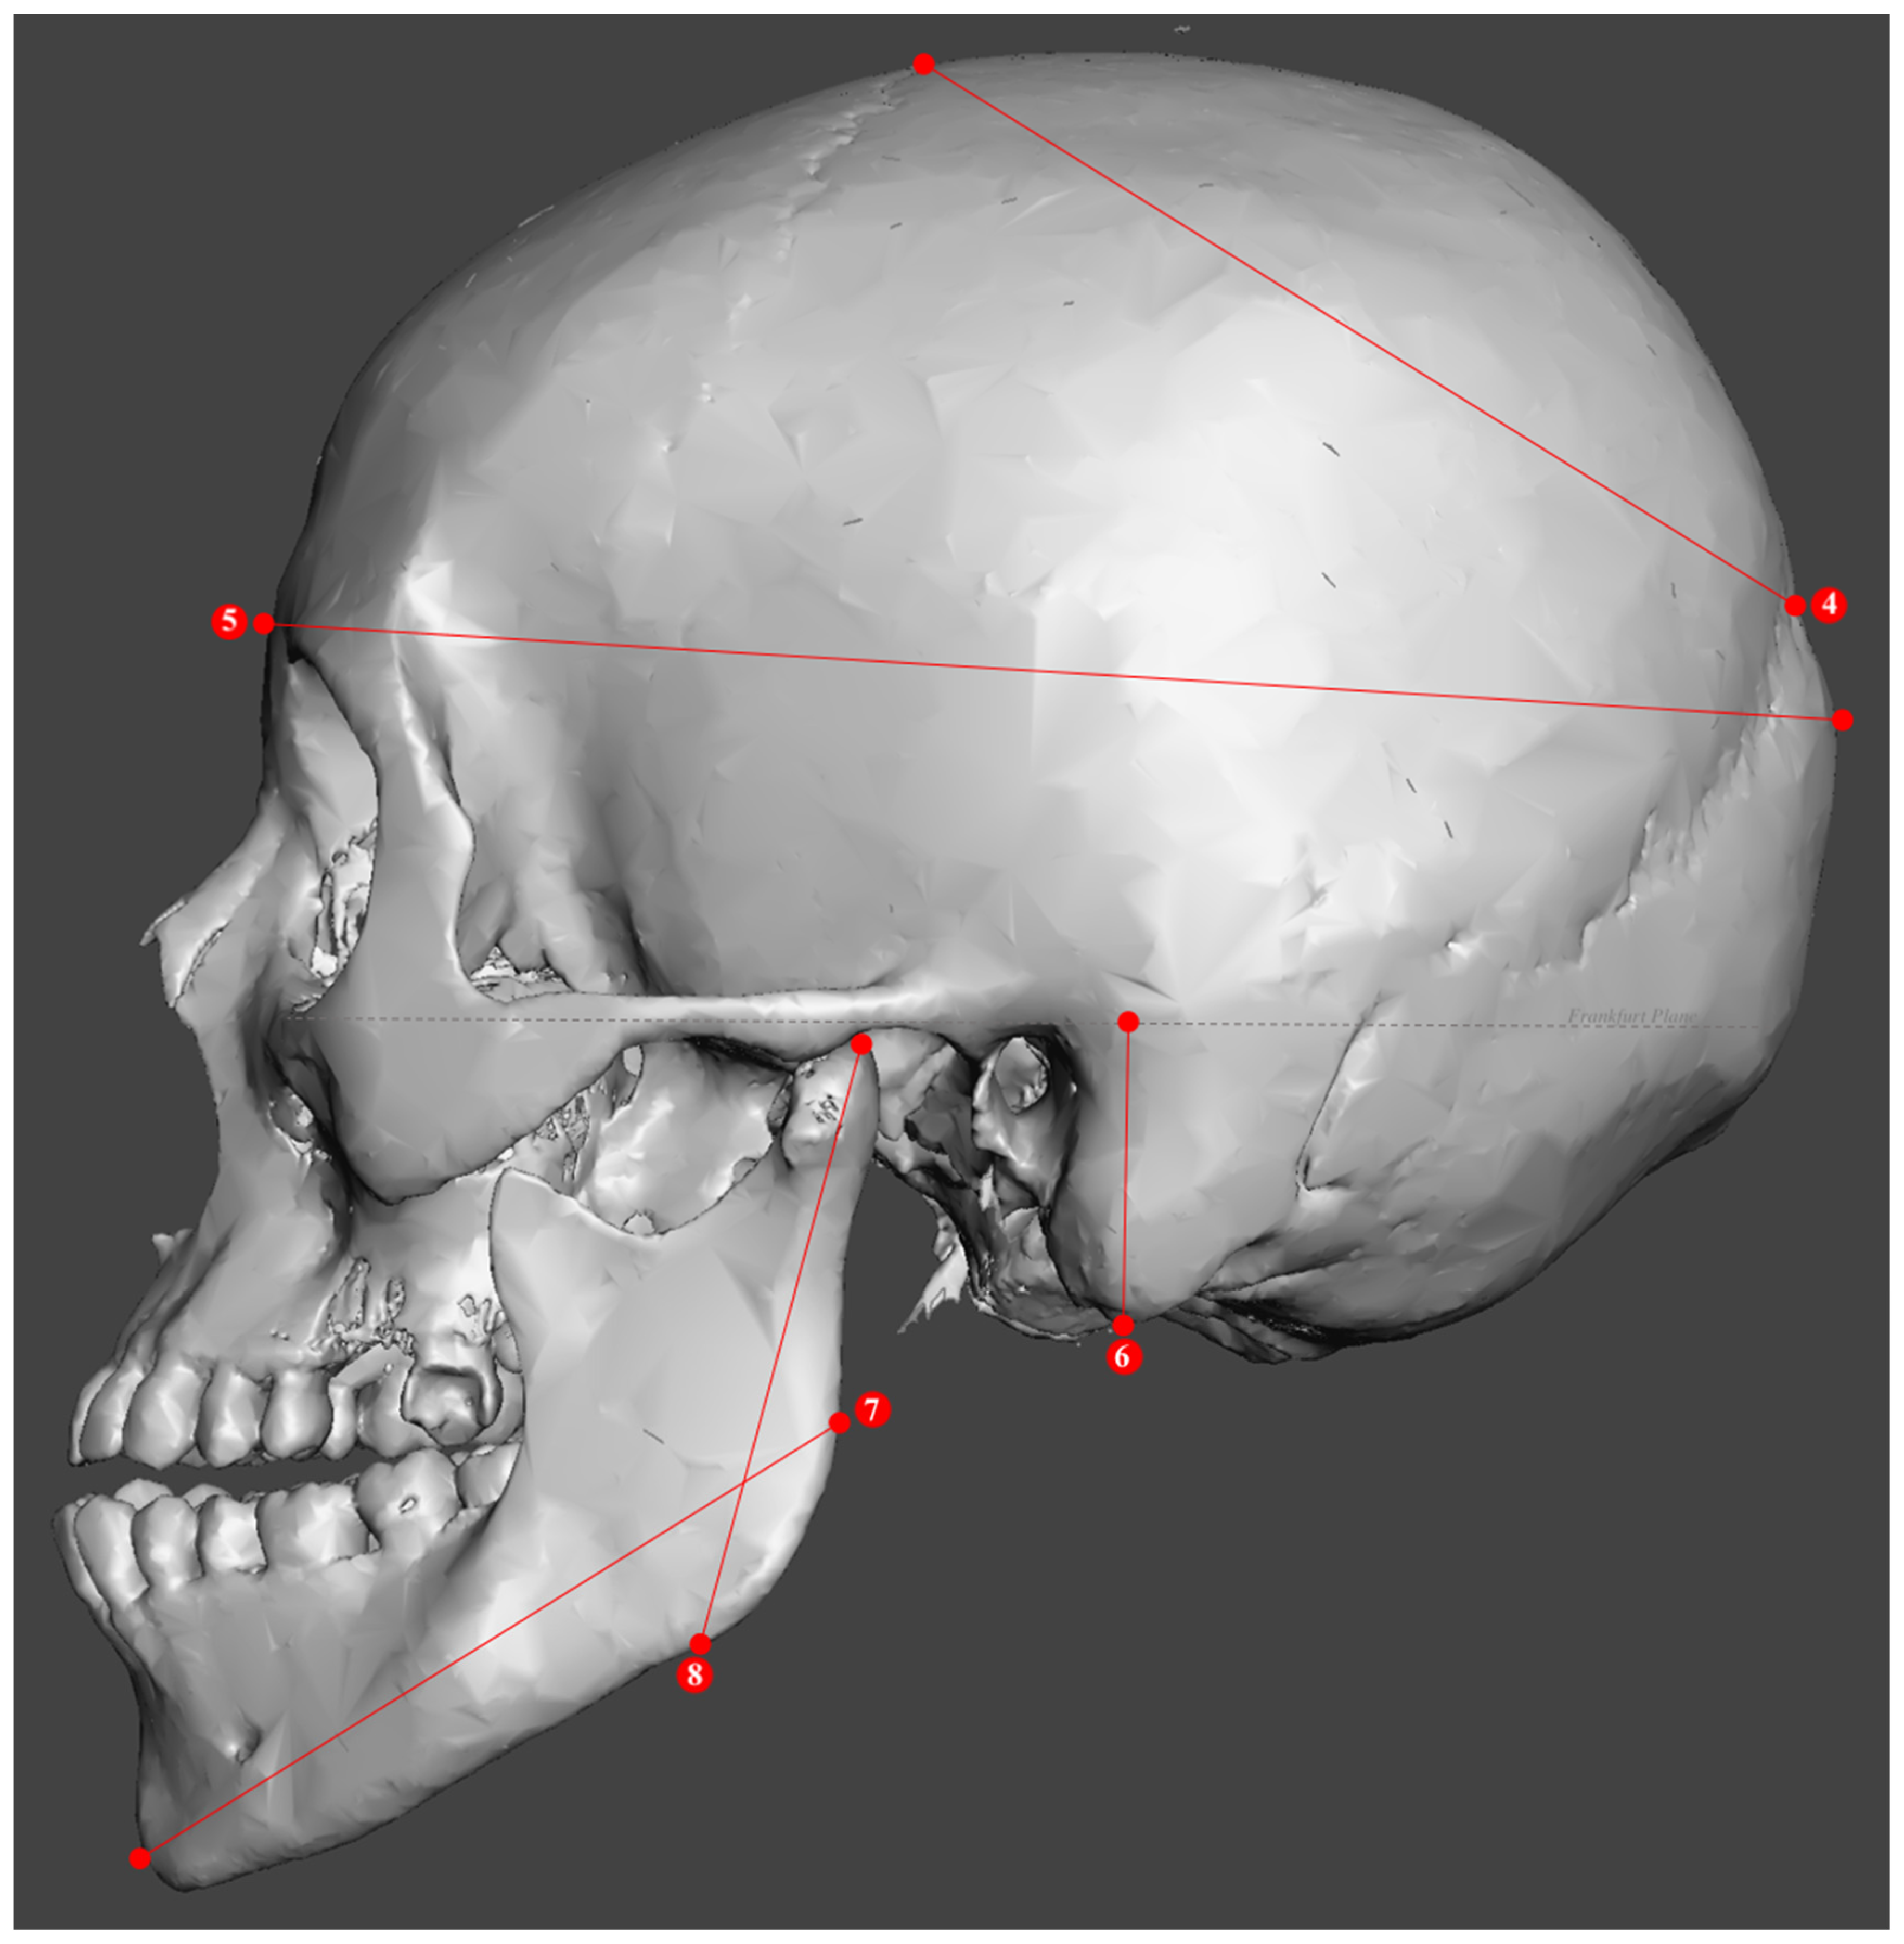

2.2. Study Sample Preparation and Data Collection

| Metric Measurements | |

|---|---|

| 1. Minimum frontal breadth (ft-ft) | 10. Bicondylar breadth (cdl-cdl) |

| 2. Orbital height | 11. Biauricular breadth (au-au) |

| 3. Upper facial height (n-pr) | 12. Foramen magnum breadth |

| 4. Parietal chord (b-l) | 13. Occipital chord (l-o) |

| 5. Glabella occipital length (g-op) | 14. Bigonial breadth (go-go) |

| 6. Mastoid length | 15. Basion–bregma height (ba-b) |

| 7. Mandibular length | 16. Basion–nasion length (ba-n) |

| 8. Maximum ramus height | 17. Frontal chord (n-b) |

| 9. Bizygomatic breadth (zy-zy) | 18. Nasal height (n-ns) |